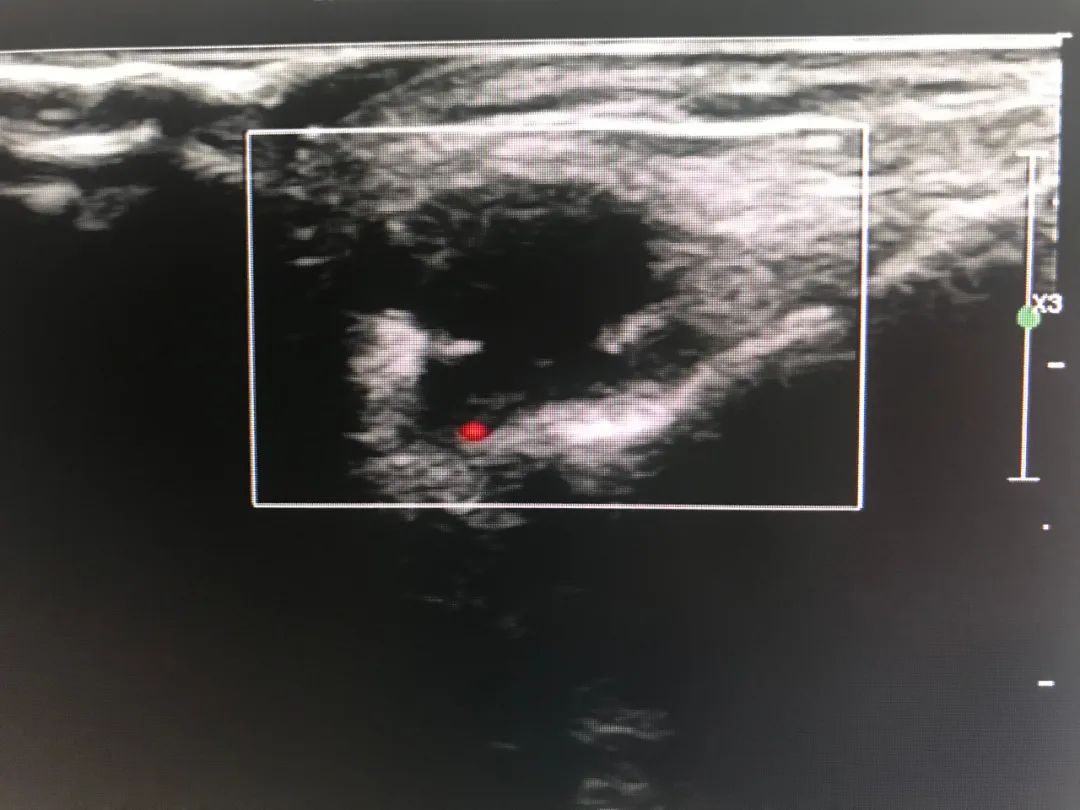

如果囊肿很容易触摸到,通过门诊透照即可方便地鉴别腱鞘囊肿与实体瘤:腱鞘囊肿透照阳性,而实体瘤透照呈阴性。 可采用超声检查帮助诊断腱鞘囊肿。大多数腱鞘囊肿边界清晰、厚壁和回声增强。实性外观的腱鞘囊肿虽然不常见,但可能酷似良性肿瘤。 在隐匿性腕部疼痛患者中,磁共振成像可区分大多数腱鞘囊肿与其他类型的肿块。

左图为手术前,右图为术后半年复发,比原来更大的囊肿